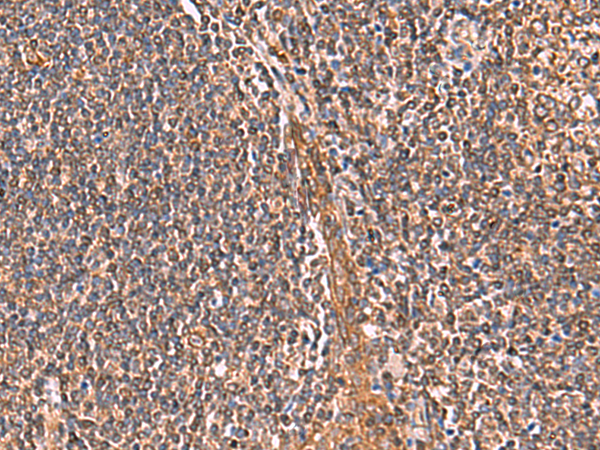

The image is immunohistochemistry of paraffin-embedded Human tonsil tissue using 47680(IFNA1/IFNA13 Antibody) at dilution 1/35.(Original magnification: 200)

The image is immunohistochemistry of paraffin-embedded Human liver cancer tissue using 47680(IFNA1/IFNA13 Antibody) at dilution 1/35.(Original magnification: 200)